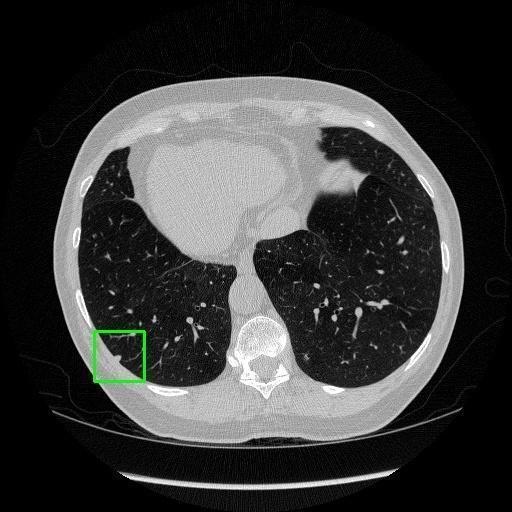

We developed an AI-based system using deep learning models for analyzing lung CT scans to detect and classify pulmonary nodules. We chose the YOLOv11 architecture for its enhanced object detection capability and adapted it specifically for medical imaging, incorporating pixel-level precision and severity classification.

Classification into three severity levels with colored bounding boxes.

Designed a severity classification system that categorizes nodules into null, moderate, and severe using colored bounding boxes, assisting in rapid clinical decision-making.